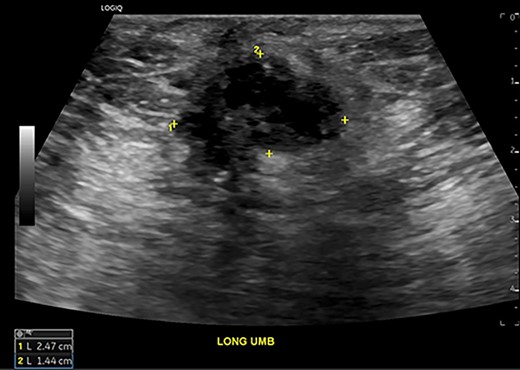

This history was suspicious for undiagnosed endometriosis with abdominal wall implantation after laparoscopic surgery. Ultrasound of the abdomen (Fig. 1) demonstrated a complex solid and cystic mass measuring 2.5 x 1.4 x 1.4 cm beneath the umbilicus without any vascular flow noted.

Abdominal ultrasound demonstrates a 2.5 x 1.4 x 1.4 cm complex solid and cystic mass at the umbilicus suspicious for trocar-site endometrioma.